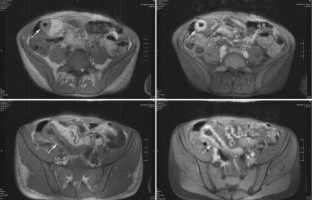

A 32-year-old male patient presented in the emergency department of our hospital with acute vomiting and diarrhoe. He reported occasional non-severe diarrhoe over several years in the past. Furthermore, at the time of presentation the patient had had anuria for several days. A prerenal and postrenal origin of the renal failure was excluded. A renal biopsy was performed and histopathological examination displayed findings consistent with a haemolytic-uraemic syndrome but no signs of glomerulonephritis. MRI examination of the small bowel revealed inflammatory alterations typical for Crohn’s disease, even without histological verification. We describe haemolytic-waemic syndrom as manifestation of Crohn’s disease for the first time.

Abb. 1